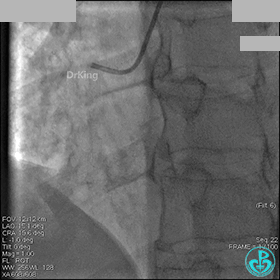

冠脉造影

入院次日冠脉造影显示粗大左主干末端中度狭窄,前降支开口严重狭窄,回旋支与前降支角度大,弥漫性长病变,严重狭窄,粗大右冠脉近中段弥漫性中重度狭窄。由于病变复杂,造影结束后先下台,择期再行介入治疗。